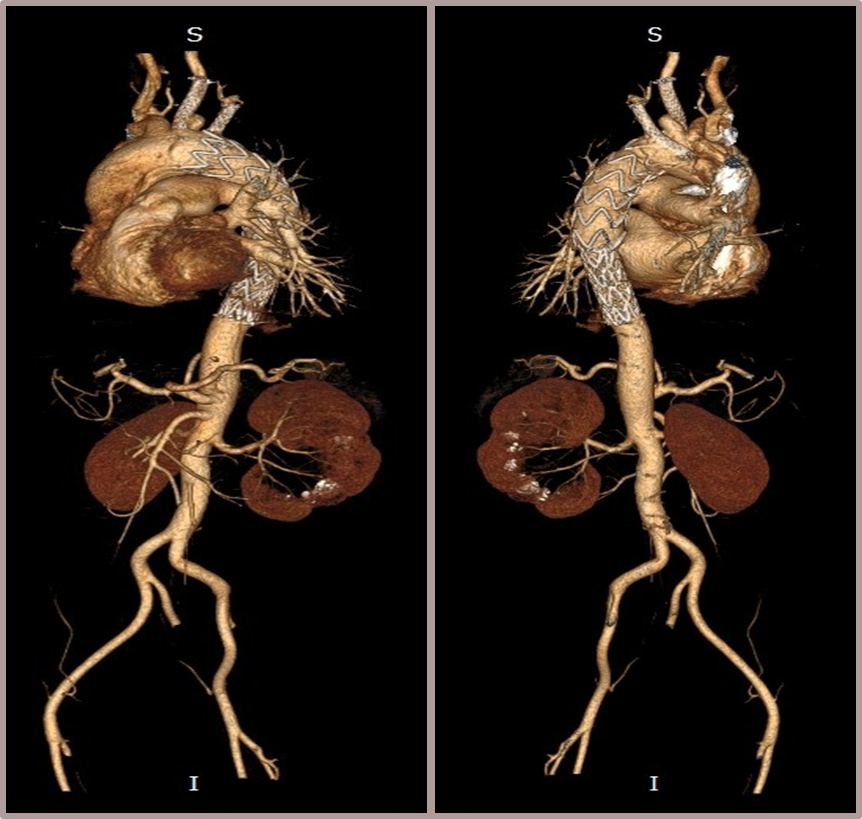

★ Case 3

男性,61岁,Bentall术后1年,主动脉弓部夹层;

既往史:高血压3级;

夹层动脉瘤CTA:A型主动脉夹层术后残余主动脉弓部夹层,头臂干及左颈总动脉根部夹层累及,向下累及胸腹主动脉至髂血管平面。

术前影像

造影后经股动脉导入并释放限制支架

经股动脉导入主体支架,抓捕无名动脉预留导丝,支架导入升主动脉

造影定位后释放主体支架

经股动脉依次超选导入分支支架,释放并球囊扩张,术毕造影

术后复查

三个穿刺点(双侧肱及单侧股动脉)无需颈部切口/穿刺

First In Man早期结果